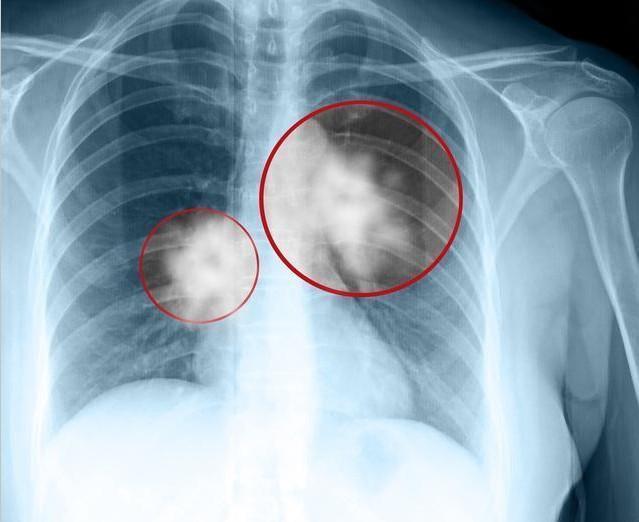

老李|46岁男子,不痛不痒,查出肺癌,手上1个标记,提示已到中晚期

可是却也一直不见好,眼见着身体日渐消瘦,老李便赶紧去医院进行检查,可是拍了胸片,也没见到任何异常。之后,医生在和老李聊天沟通情况时,发现,老李的手指尖趋于隆起,胀的像鼓槌一样,见此,医生便赶紧让老李进行肺CT检查,果不其然,医生发现了罪魁祸首,是''肺癌'',并且已到了中晚期。